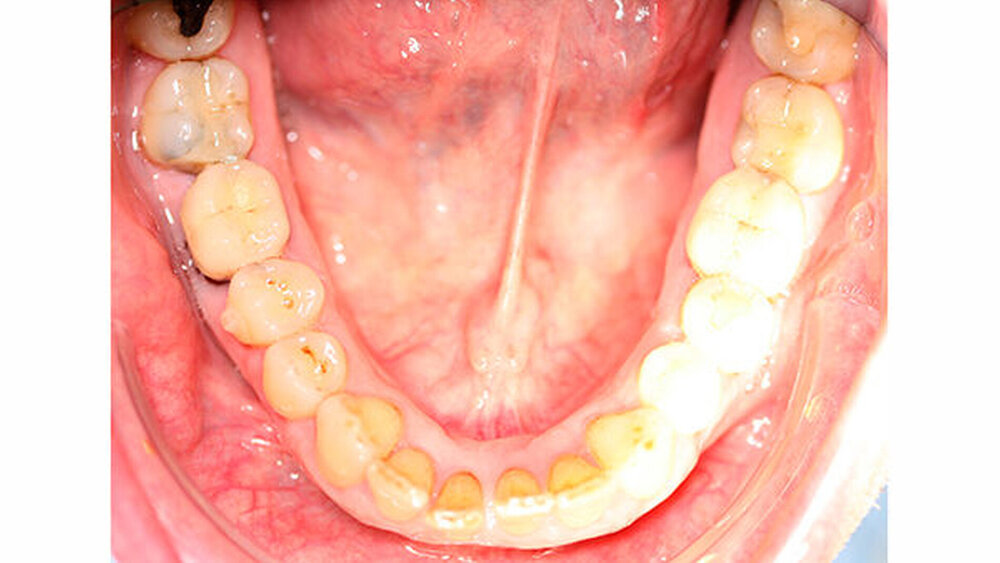

Intraoral zeigte sich ein bereits konservierend versorgtes permanentes Gebiss mit aktivem und inaktivem kariösen Geschehen. Große Anteile der Zahnhälse lagen nach Zahnfleischrückgang in Kombination mit Knocheneinbrüchen frei. Zahn 27 wurde bereits extrahiert.

Kieferorthopädisch imponierte beidseits eine neutrale Verzahnung bei einem tiefen Biss von 5 mm - bedingt durch die Verlängerung beider Frontzahngruppen. Besonders Zahn 11 zeigte eine erhebliche Verlängerung und Protrusion mit einer sagittalen Frontzahnstufe von 5 mm. Sowohl die Frontzähne im Ober- als auch im Unterkiefer wiesen eine lückige Beziehung zueinander auf (Abbildung 1).